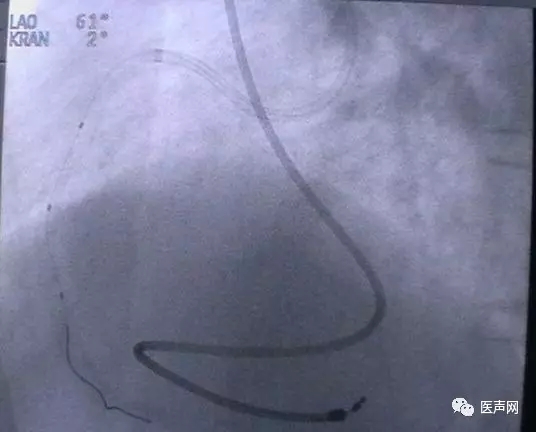

病例1: 冠脉搭桥术后,静脉桥CTO(CABG, VB-CTO)

箭头所示为第3个吻合点

(pre-PCI)

VB-对角支(jump)---LCX(jump)-PDA远端,第一个吻合以下完全阻断。

· 导引导管非常深置(Very very deep seating)(本例GC达CTO 第一吻合口前)(这是Dr. Lauer常用一招)

· 对侧造影

· 硬导丝(走得很远, 达PDA)

· 微导管,OTW 球囊.

当打通后,发生室速,电复律---出现无复流---室速---植入支架(TAXUS Liberte)

当导引导管非常深置(very very deep seating)时,你可以想象支持力有多大,永远不要忘记他做RCA-CTO时导引导管深插到RCA中段的例子。此病例实际上PDA未能开通,在6月28日 Dr. Lauer终于用类似方法打通了PDA。